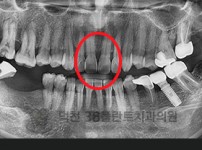

치료전후